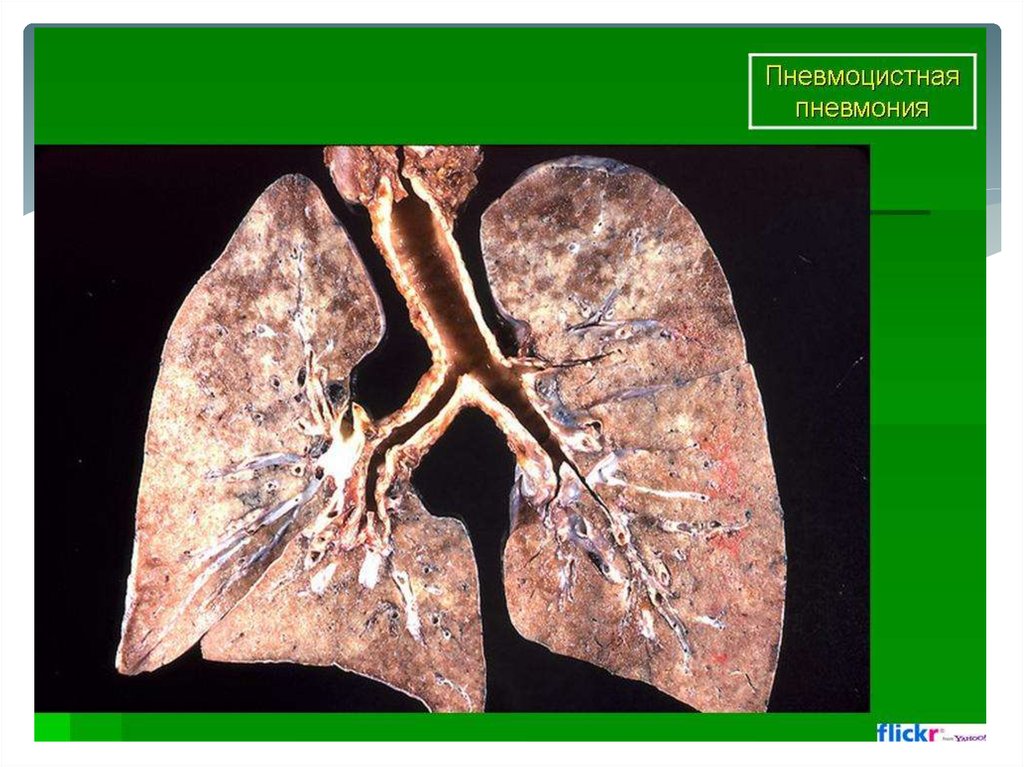

Пневмоцистная пневмония

Финальная стадия характеризуется развитием альвеолита,

изменением альвеолярного эпителия, интерстициональной

инфильтрацией эпителия. Обилие цист выявляется как в

просвете альвеол, так и внутри макрофагов.